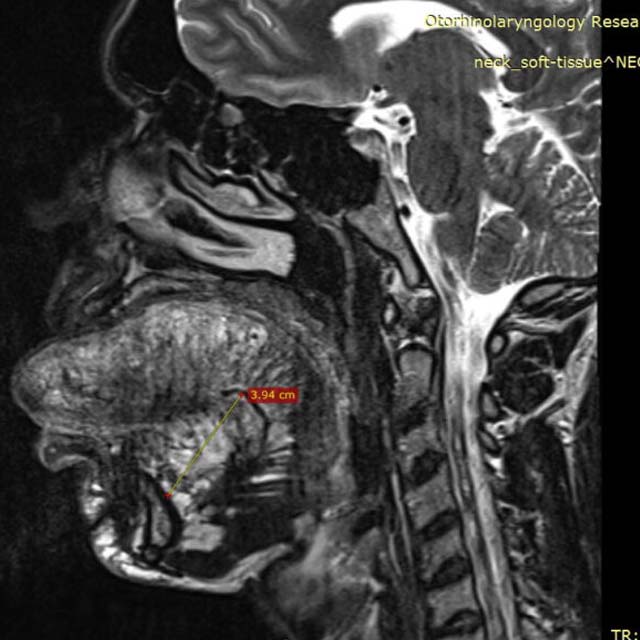

Одним из наиболее ярких клинических случаев стала история нашего пациента Кирилла Баданова, который обратился за помощью в 2018 году с участием телевизионной программы «Я стесняюсь своего тела». Кирилл всю жизнь страдал от врожденной лимфангиомы языка, доброкачественной опухоли. Операция в детском возрасте прошла неудачно. Из-за огромного размера языка, который не помещался в ротовую полость, произошла скученность зубов, несмыкание челюстей. Во избежание травмы языка пришлось удалить передние зубы.

Гигантских размеров лимфангиома значительно снижала качество жизни молодого человека, создавала трудности жевания пищи и речи. Страдала личная жизнь Кирилла, который не мог завести семью из-за выраженного эстетического дефекта.

Ситуация осложнялась тем, что опухоль начала увеличиваться в размерах и проникать в соседние ткани. Операцию откладывать было нельзя. Но многие клиники отказывали в проведении хирургического лечения Кириллу. Письмо редакции программы «Я стесняюсь своего тела» поступило в НМИЦО ФМБА России к доктору Давиду Назаряну. После первого осмотра и консультации Кирилл Баданов полностью доверился команде хирургов отделения.